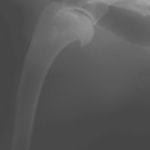

症例:トイプードル 9カ月齢

3ヵ月前より左前肢の跛行が認められるとのことで、来院されました。整形外科学的検査において、患肢の肘関節・肩関節重度の伸展制限が認められました。Xray検査において、左肩関節の内方脱臼、および肩甲骨関節窩の低形成と上腕骨頭の変形が認められました。

数か月に及ぶ慢性脱臼のため、関節面の低形成・摩耗のため整復手術による適切な再建は困難と判断し、切除関節形成術を実施しました。

術後3週間頃より、負重状態、歩行が改善しました。

切除関節形成術は、疼痛を引き起こす関節面を除去し、線維性偽関節の形成により患肢の機能改善を促す救済的手術です。術後のリハビリテーションの実施により、関節の可動域や患肢の筋肉量は改善され、生活の質は向上します。また本症例のように、慢性脱臼だけでなく、重度の骨関節炎症例にも実施することがあります。